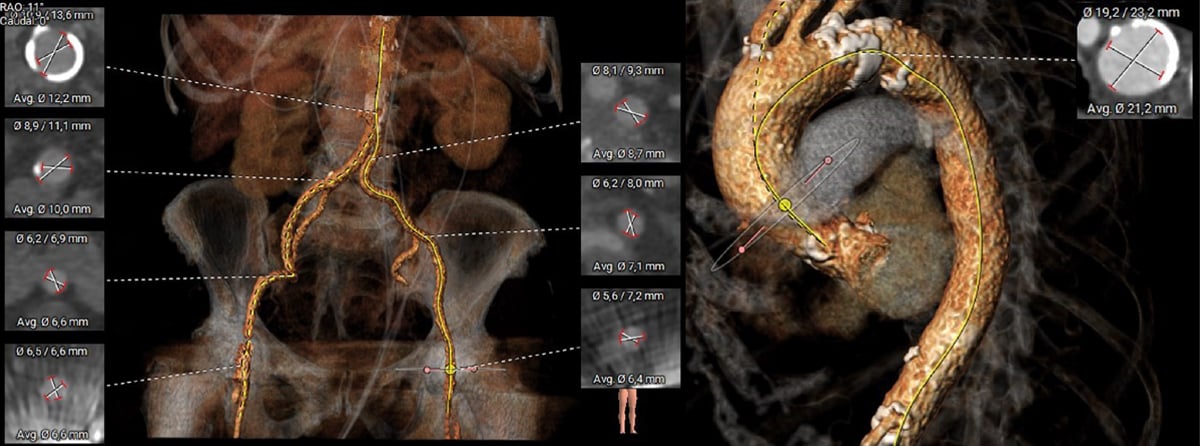

Die Planungs-Computertomographie (Abbildung 2-6) zeigte eine stark verkalkte Aortenklappe (Agatston-Score 3.398, Kalziumvolumen 2.627) mit leicht asymmetrischen Taschenklappen, wobei die nichtkoronare Tasche die größte war. Der linksventrikuläre Ausflusstrakt (LVOT) war verkalkt, beginnend auf Annulusebene bis 5,1 mm in den LVOT unterhalb der linkscoronaren Tasche reichend. Die Aortenwurzeldiameter waren niedrig: Anulus (aus dem Perimeter abgeleiteter Durchmesser 22,3 mm), linker ventrikulärer Ausflusstrakt (LVOT) bei 4 mm (19,9 mm), Sinus valsalva (SOV) (links 24,4 mm, rechts 25,3 mm, noncoronar 27,3 mm) und sinutubulärer Übergang (STJ) (24,0 mm). Darüber hinaus zeigte sich ein geringer Abstand des Ostiums der linken Koronararterie zum Annulus (8,6 mm) und eine horizontale Aorta (74°). Die Aorta, die Iliaca und die Femoralarterien waren für einen transfemoralen Zugang geeignet.

Abbildung 5: Computertomographie - Gefäßzugang

Die kontrastmittelverstärkte Computertomographie zeigte spezifische anatomische Herausforderungen: a) trikuspide Aortenklappe mit massiver Verkalkung (Agaston-Score 3,398), b) Verkalkungen des linkskoronren Annulus bis in den linksventrikulären Ausflusstrakt (LVOT) reichend, c) kleiner Aortenklappenannulus mit einem Durchmesser von 22 mm und schmalem 19 mm LVOT, d) kleine Aortenwurzeldimensionen, d) 8.6 mm Abstand des LCA-Ostiums zur Annulusebene und e) eine 74° horizontale Aorta.